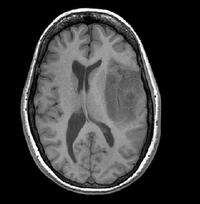

1

RegLib C01: MR Meningioma Align baseline MR of meningioma with follow-up.

brain tumor rigid+ affine MRI RegLib_C01.mrb

(input data only , Slicer mrb file. 13 MB)